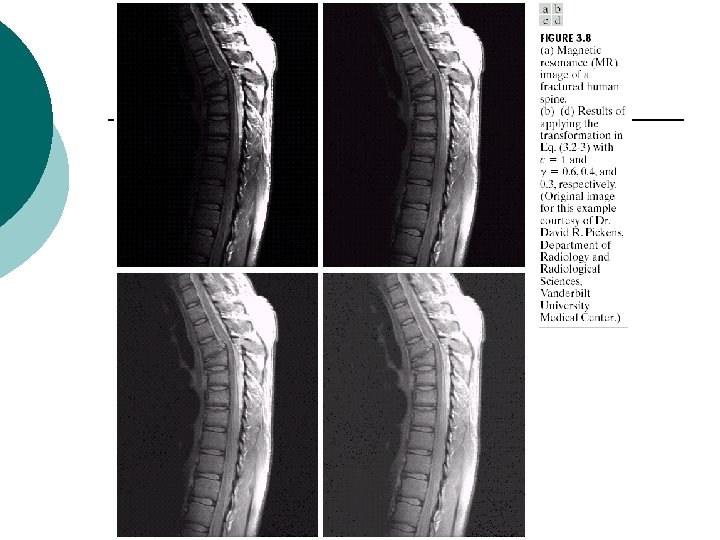

Power-law transformations ¡ or ¡ l l maps a narrow range of dark input values into a wider range of output values, while maps a narrow range of bright input values into a wider range of output values : gamma, gamma correction